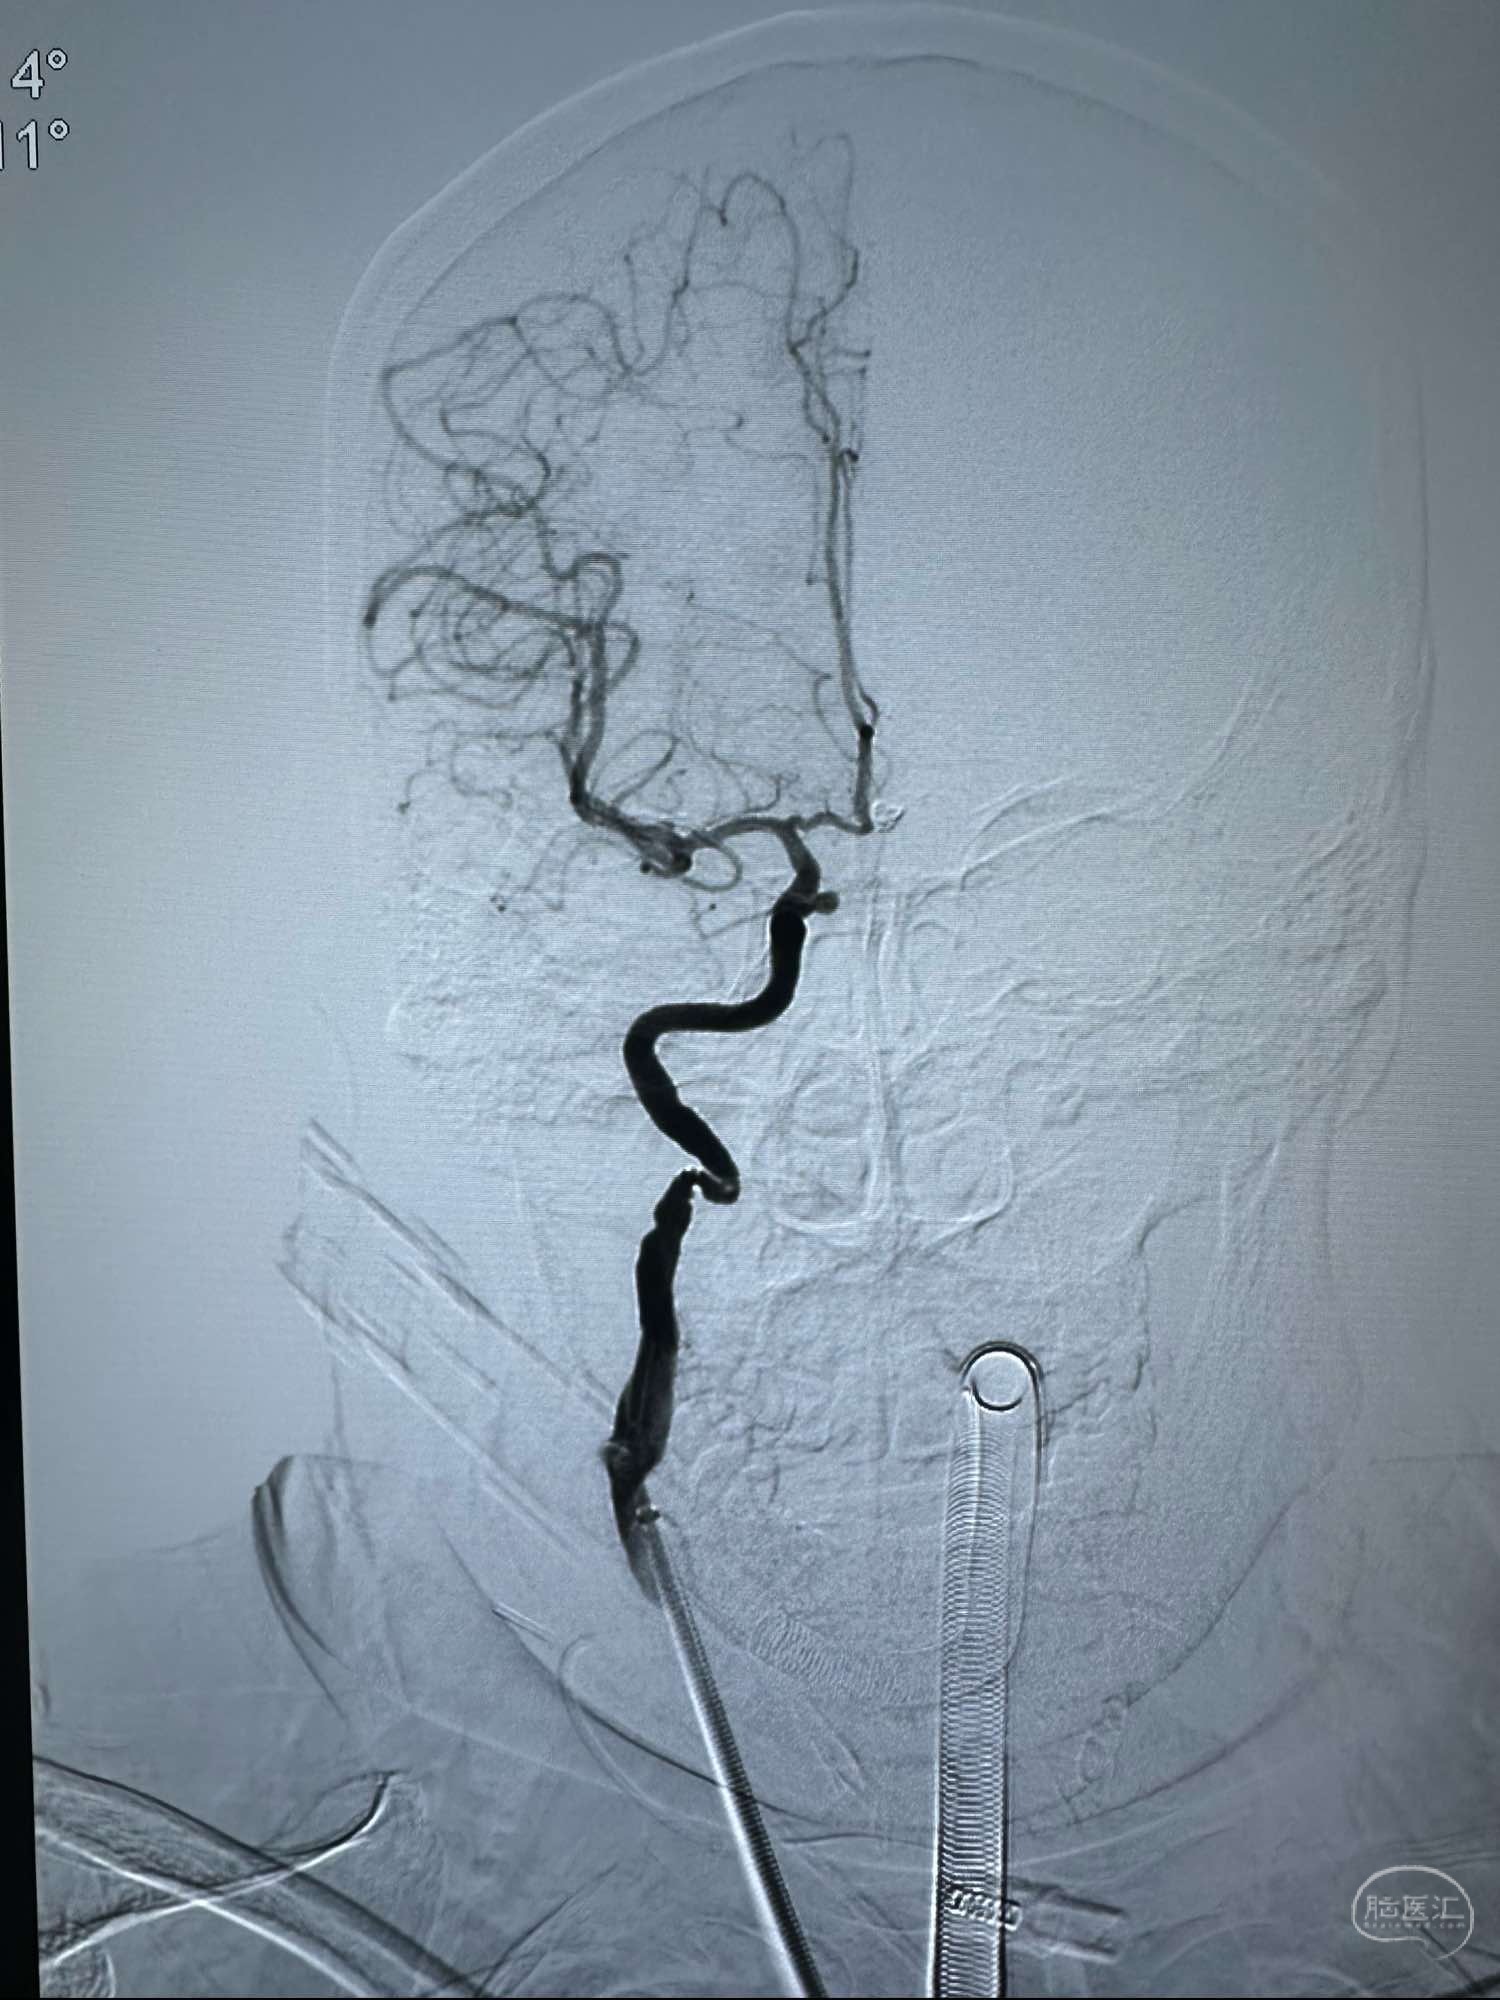

术前的右侧颈内动脉正位造影

术前的右侧颈内动脉正位造影